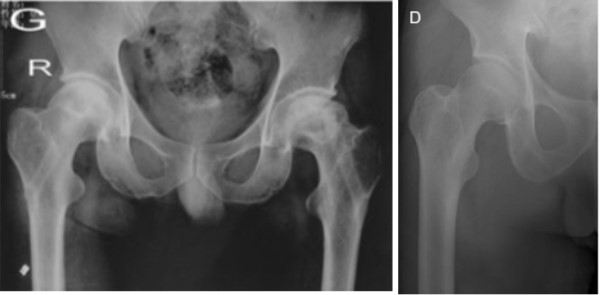

1.良好的减压效果,有效改善血液循环

2.生物活性材料结合植骨,增强骨融合

3.提供足够的力学支撑,防止股骨头塌陷

● 股骨头I、II期坏死3.提供足够的力学支撑,防止股骨头塌陷